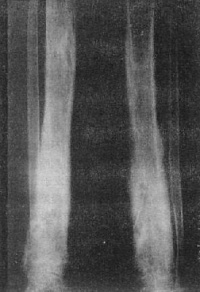

X线照片可显示死骨及大量较致密的新骨形成,有时有空腔,如系战伤,可有弹片存在。布劳德氏脓肿X线照片显示长骨干骺端有圆形稀疏区,脓肿周围骨质致密。加利氏骨髓炎骨质一般较粗大致密,无明显死骨,骨髓腔消失。